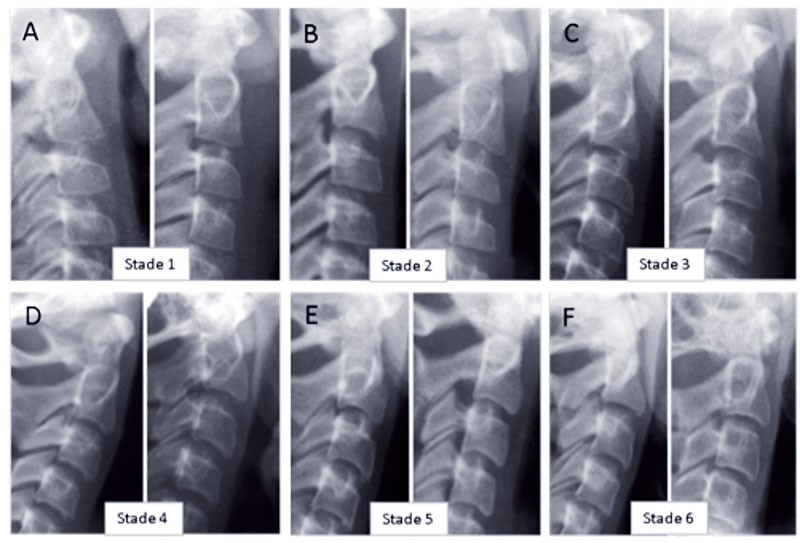

Cette méthode, mise au point par Lamparski en 1972 et simplifiée par Baccetti et McNamara, permet de déterminer le moment optimal de début de traitement. En évaluant la maturation des vertèbres cervicales sur des téléradiographies de profil grâce à leur forme il est possible de situer le patient sur sa courbe de croissance. Selon la forme des corps vertébraux de C2, C3 et C4 et de leur bord inférieur on distingue 6 stades de maturation vertébrale (fig. 1 et 3).